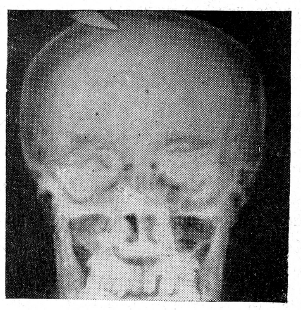

В январе 1959 г. при надевании противогаза отметил резкие боли в области рубца на левой половине головы. Обратился к врачу, который назначил ему рентгенографию черепа. На рентгенограммах черепа, неожиданно для больного и врача, был обнаружен (рис. 1 и 2) отломившийся кончик ножа размером 4,5х1,2 см, проникающий через обе пластинки левой теменной кости в полость черепа на глубину около 1 см. Инородное тело расположено в среднем отделе теменной кости на расстоянии около 4 см от стреловидного шва.

Рис. 2. То же (профильный снимок).